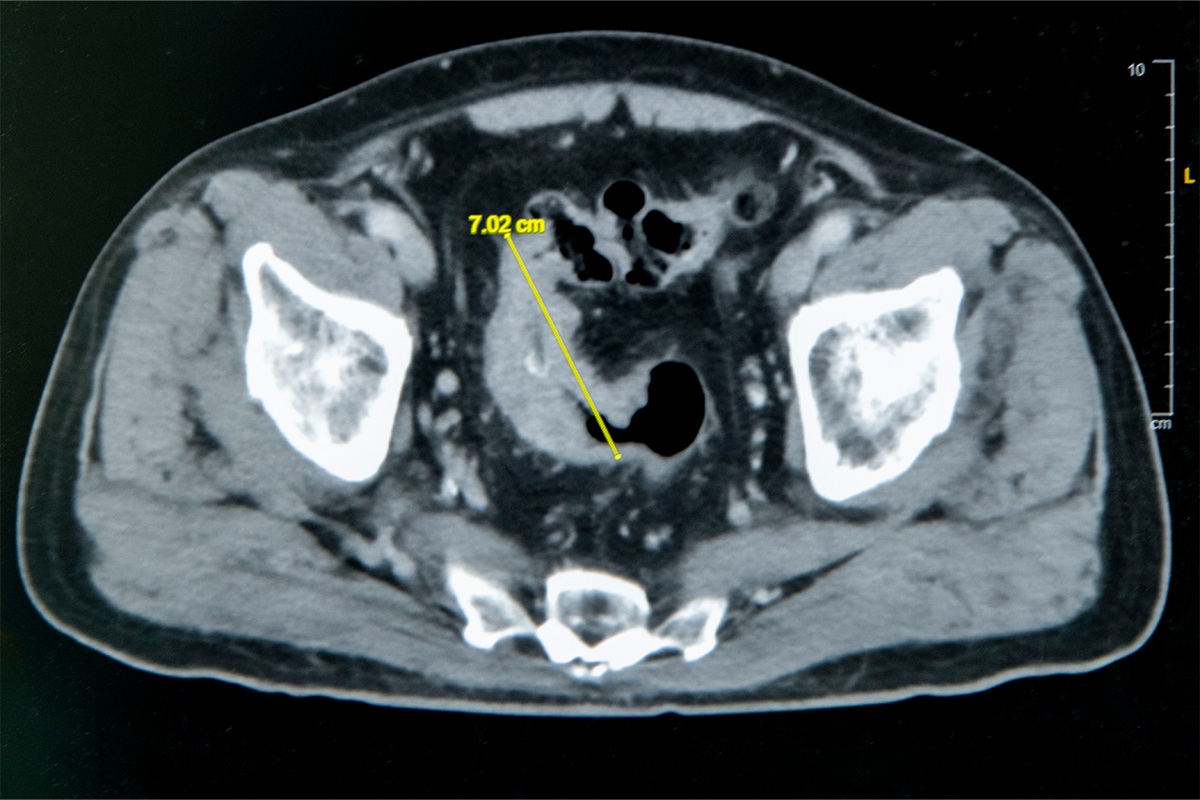

大腸直腸外科主任張譽耀醫師表示,老翁罹患乙狀結腸癌,腫瘤約7公分造成腸子幾乎完全阻塞,也導致老翁一進食就會肚子又脹又痛;術前因為不敢進食,老翁體重下降、營養不足,也可能造成傷口癒合不良。老翁的手術其實會有兩個傷口,一個是肚子上的傷口、一個腸子的傷口,若腸子傷口癒合不良會造成腸吻合滲漏,到時就必須做人工肛門了!所幸經過提早住院,透過靜脈營養針先建立營養,讓病人強健身體後才手術,術後傷口果然順利癒合。

▲老翁罹患乙狀結腸癌,腫瘤約7公分造成腸子幾乎完全阻塞。(圖/彰基提供)